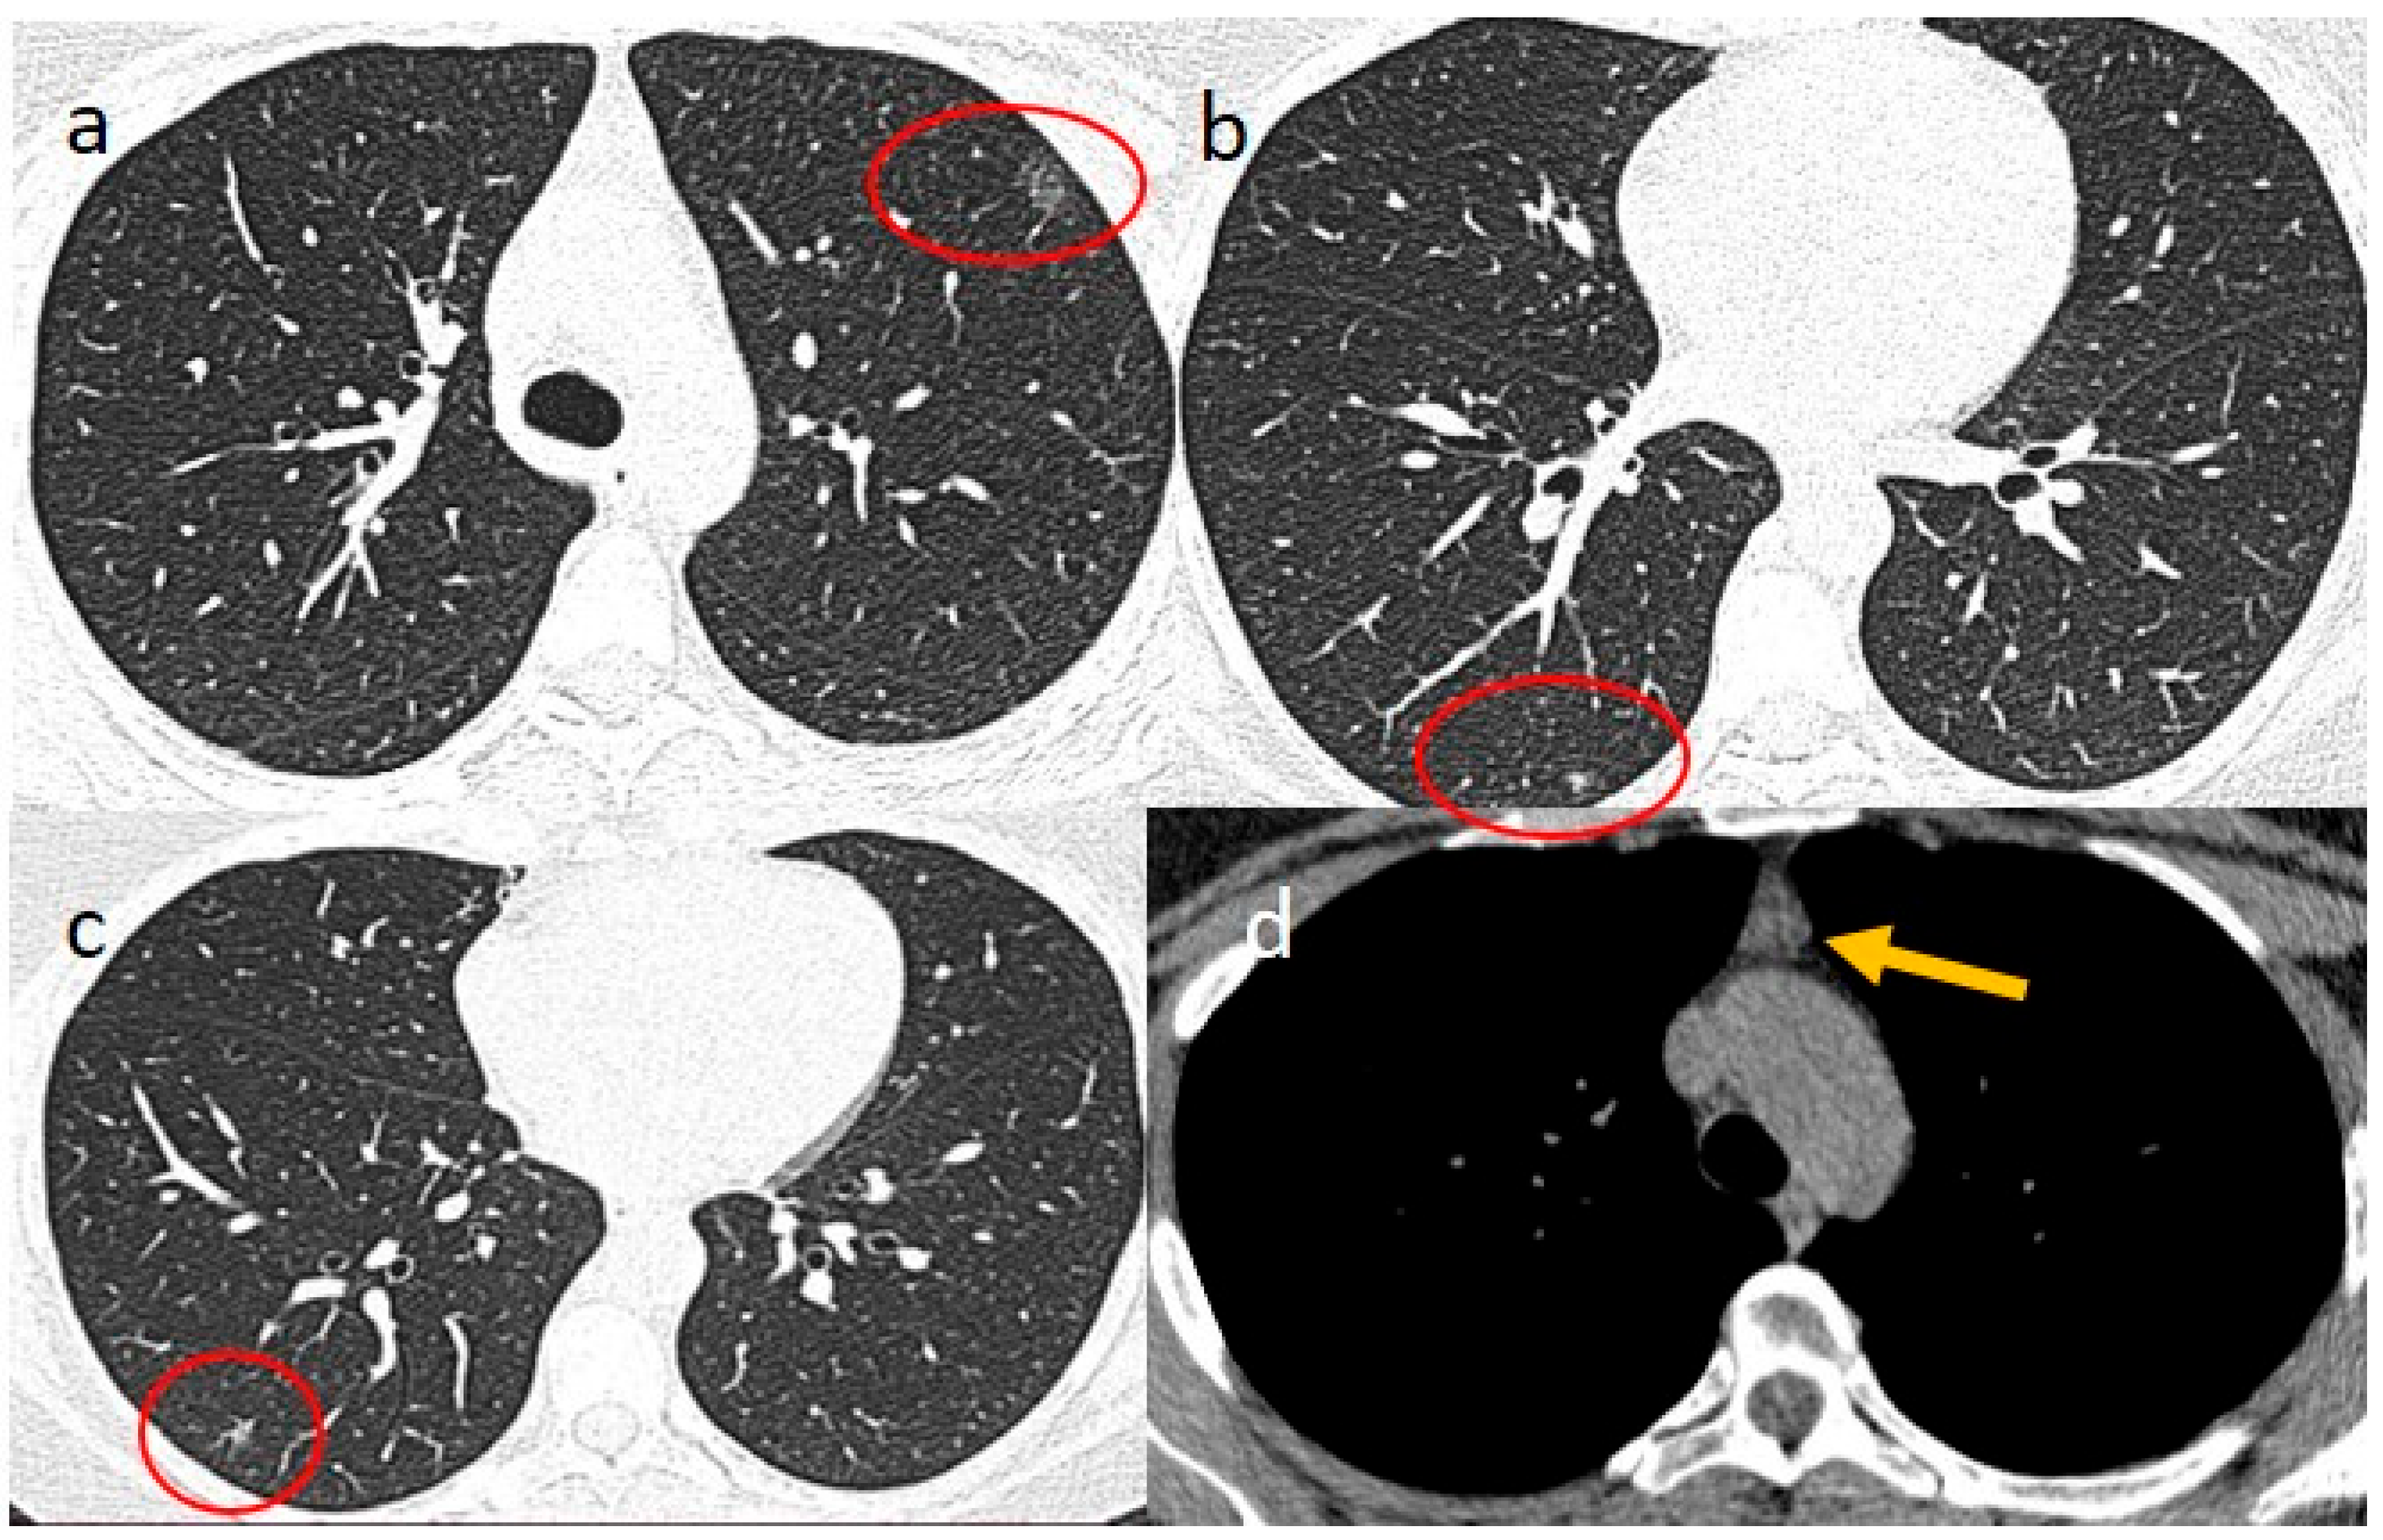

2. Case Presentations

3.2. Thymic Hyperplasia in COVID-19 Infection and Vaccination and the Role of Multimodality Imaging